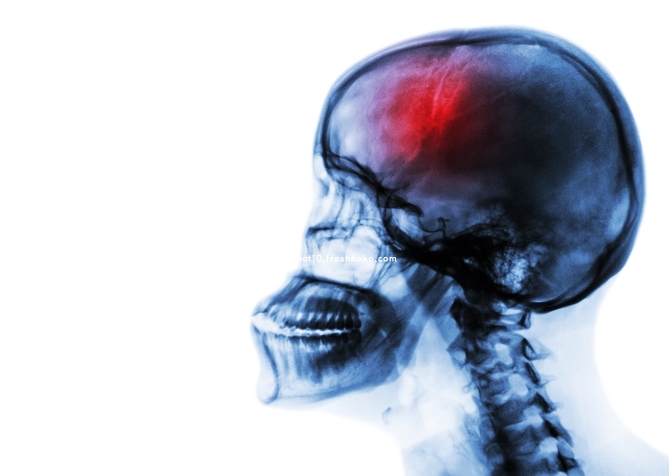

뇌졸중은 빠르면 빠를수록 생존율이 높아지며, 후유증을 줄일 수 있습니다. 특히 고혈압, 당뇨, 고지혈증, 심방세동 등의 만성질환이 있는 분들이나 흡연, 음주, 스트레스 등 위험요인이 있는 분들은 더 세심한 주의가 필요합니다.

또한 뇌졸중은 고령층에게만 발생하는 질환이 아닙니다. 최근에는 30~40대에서도 발생률이 높아지고 있으므로, 누구나 이 다섯 가지 전조증상은 꼭 기억해두셔야 합니다.

"얼굴이 이상해요, 팔이 안 올라가요, 말이 꼬여요, 시야가 이상해요, 머리가 너무 아파요." 이 다섯 가지 중 하나라도 해당된다면 절대 지체하지 마시고 즉시 응급조치를 받으시길 바랍니다.